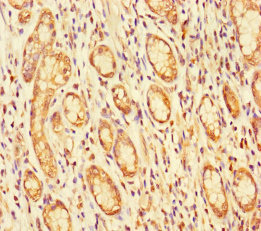

ApplicationELISA, IHC; Recommended dilution: IHC:1:20-1:200